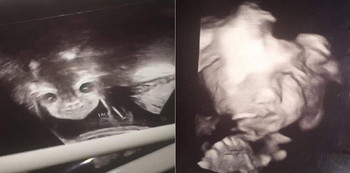

Baby ultrasound ng isang buntis nagpakita ng nakakakilabot ngunit cute na larawan ng kaniyang sanggol.

Magkahalong excitement at kilabot ang naramdaman ng isang 17-anyos na buntis na si Iyanna Carrington at ng kaniyang mister ng sila ay magpunta sa doktor at tingnan ang kaniyang baby ultrasound. Dahil imbis na malaman lang ang kasarian ng kaniyang baby ay na-tiyempuhang napatingin ito sa ultrasound scan at naka-dilat pa.

baby ultrasound

Image from Fox News

Mukha mang kakaiba, siniguro naman ng doktor at technician na nagsagawa ng ultrasound na normal itong nangyayari sa mga baby ultrasound scan.

Ibinahagi ni Iyanna ang larawan ng kaniyang baby ultrasound sa Facebook na kung saan shinare na ito ng higit sa 16,000 times.

Sa kaniyang post ay ito ang nasabi niya:

“She was looking normal then we found out she was a girl they put it back on her face then her a– opened her eyes and smiled. I love this devil baby so much already.”